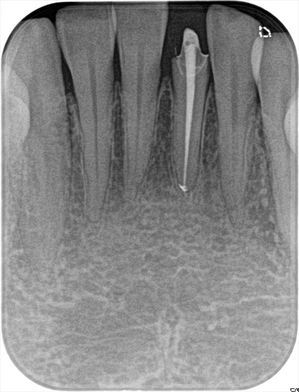

2020.02.14_R27.jpg

本日、垂直加圧根管充填後のデンタルX線写真です。

細くて長い歯ではありますが、先端まで充填出来て安堵する瞬間です。

U・Yさん、再根管治療もいよいよこの歯で終了ですね。